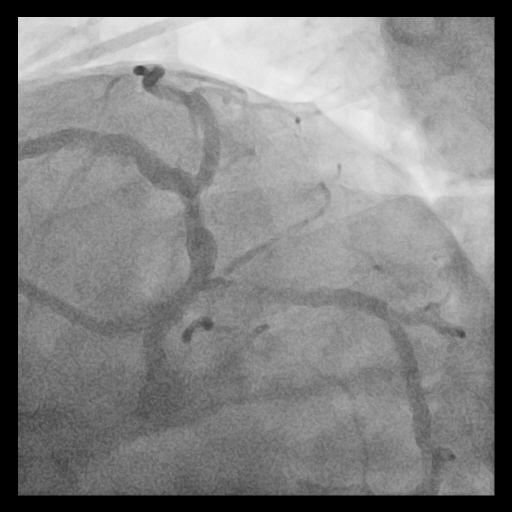

Relevant Catheterization Findings

Coronary angiography showed long, tram-track dense calcification involving the left main bifurcation with subtotal occlusion of proximal LCx and diffuse proximal LAD disease. The calcified plaque exhibited significant radiopacities visible before contrast injection, suggesting a deep concentric calcium burden.

Given the extensive and concentric calcium across the LM bifurcation, an upfront ¡°Rotatripsy¡± strategy (rotational atherectomy followed by intravascular lithotripsy) was selected. A 1.25 mm burr was used for initial channel creation in the LCx and LM-LAD, with transient bradycardia requiring temporary pacing. Post-rotablation IVUS revealed residual deep calcium. Subsequently, intravascular lithotripsy (IVL) using a 3.5–4.0 mm balloon (1:1 sizing to proximal LCx and LM) was applied with 8 cycles, achieving clear calcium fracture on IVUS. Two DES were implanted sequentially (LCx: 3.5¡¿28 mm; LM–LAD: 4.0¡¿38 mm), followed by high-pressure post-dilation and final kissing balloon inflation. Final IVUS confirmed optimal stent expansion (MSA: LCx 7.7 mm©÷, LAD 12.1 mm©÷, LM 13.2 mm©÷) and well-apposed stents throughout the bifurcation.